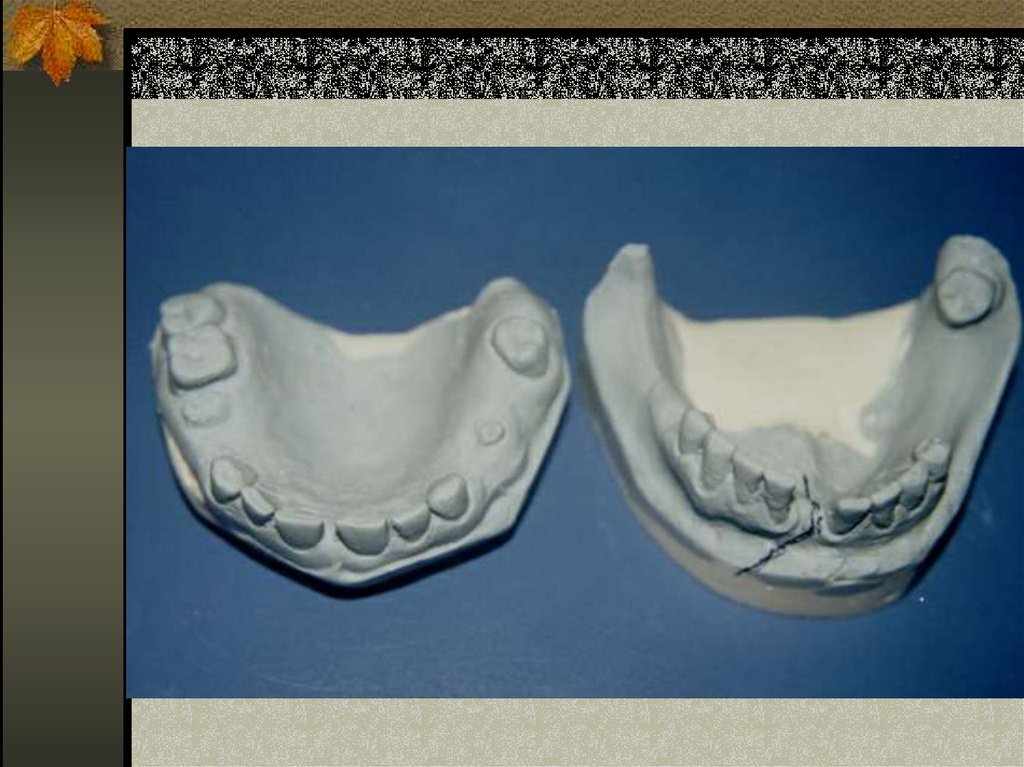

12. ateller

Hijyenik bakımın zorluğu, beslenme

güçlükleri, genel anestezi altında

uygulanmasının imkansızlığı, dişsiz

veya az sayıda dişli olanlara

uygulanamaması dezavantajlarıdır.

Atellerle çeneler arası blokajda iyileşme

dişlerin karşılıklı temaslarının

mükemmelliği oranında tatminkardır.